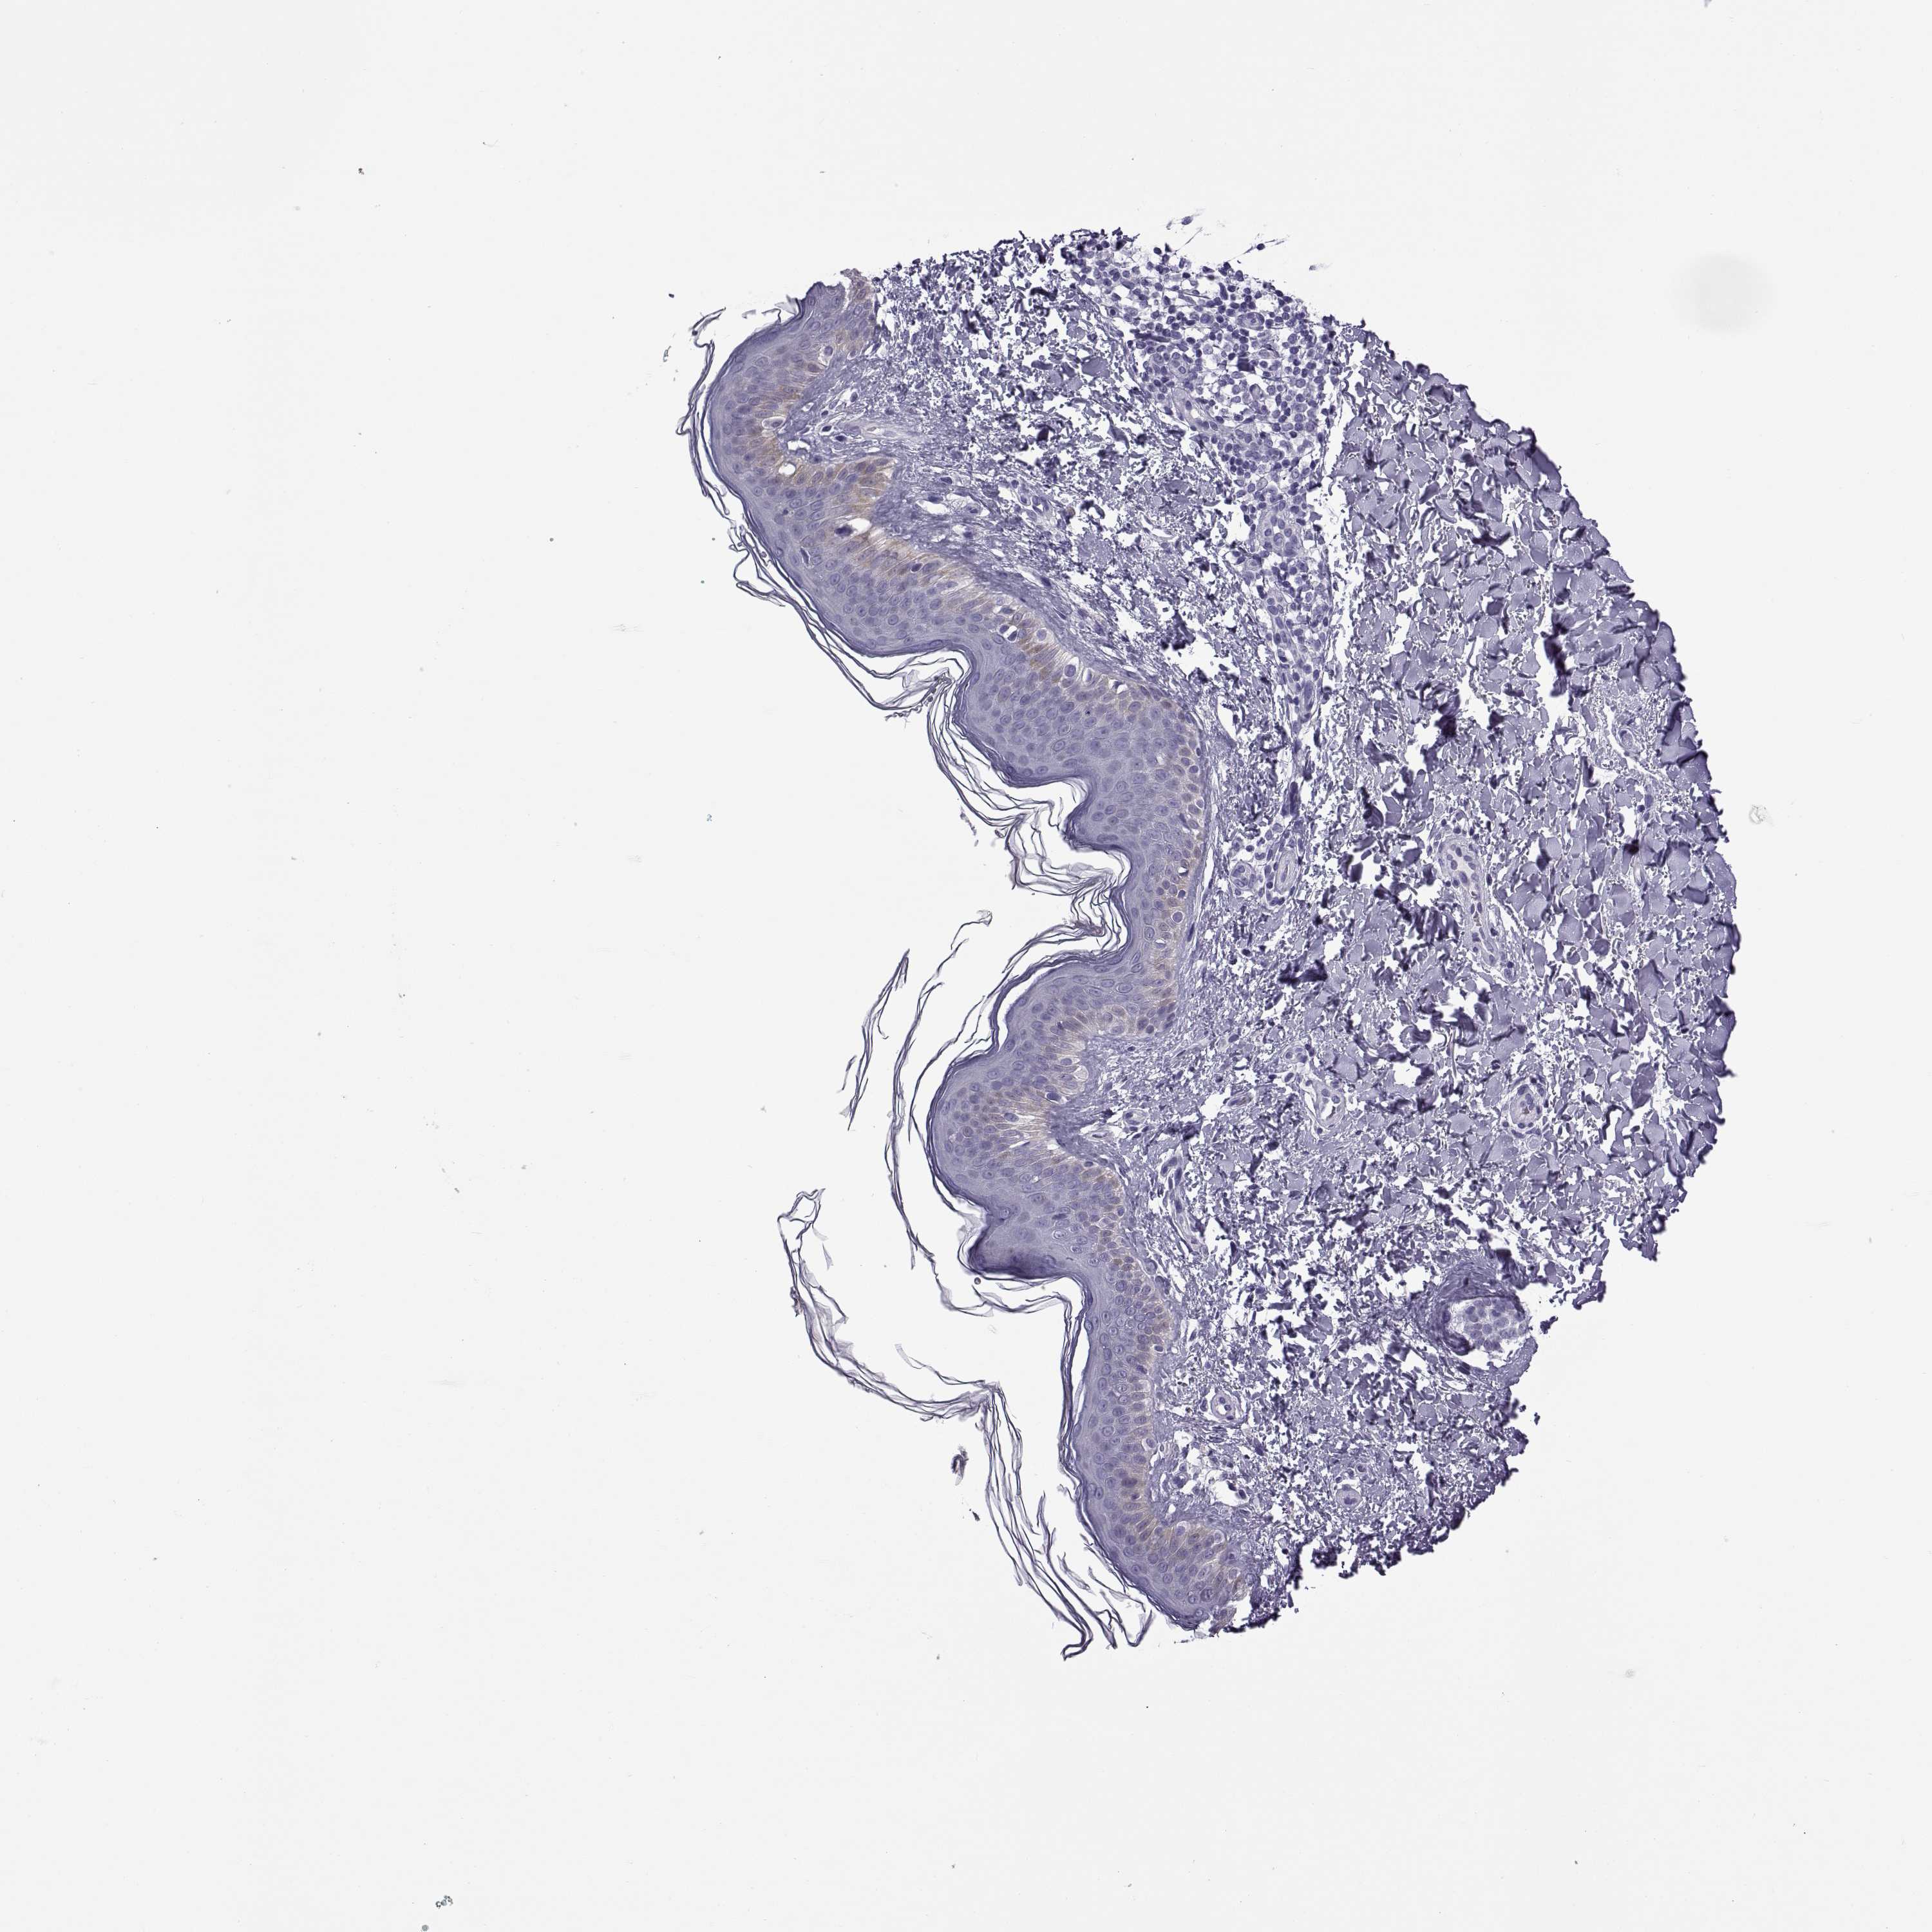

Basal cell and squamous cell cancer

SKIN CANCER - Protein expressioni

A mouse-over function shows sample information and annotation data. Click on an image to view it in a full screen mode. Samples can be filtered based on level of antibody staining by selecting one or several of the following categories: high, medium, low and not detected. The assay and annotation is described here.

Antibody stainingi

Antibody staining in the annotated cell types in the current human tissue is reported as not detected, low, medium, or high, based on conventional immunohistochemistry profiling in selected tissues. This score is based on the combination of the staining intensity and fraction of stained cells.

Each image is clickable and will lead to virtual microscopy that enables deeper exploration of all samples and also displays staining intensity scores, fraction scores and subcellular localization as well as patient and tissue information for each sample.

Antibody HPA052271

Antibody HPA059602

Staining

High

Medium

Low

Not detected

Intensity

Strong

Moderate

Weak

Negative

Quantity

>75%

75%-25%

<25%

None

Location

Nuclear

Cytoplasmic/membranous

Cytoplasmic/membranous,nuclear

Basal cell carcinoma

Squamous cell carcinoma, NOS